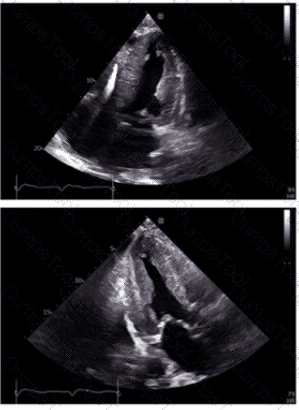

What is the regional wall motion assessment of the two-chamber view displayed in this video?

Which coronary artery territory is associated with the wall motion abnormality demonstrated in this video?